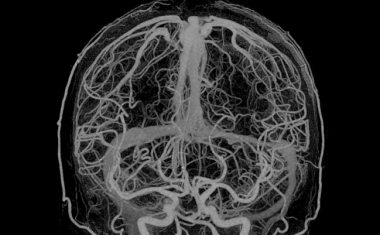

Eine neue Angiografieanlage ermöglicht Eingriffe auch an kleinen Hirngefäßen, dank modernster Vergrößerungstechnik.

„Die Kombination aus UHR und KI bringt uns auf ein neues diagnostisches Level“, fassen Prof. Dr. Marc Brockmann und Prof. Dr. Ahmed Othman zusammen.